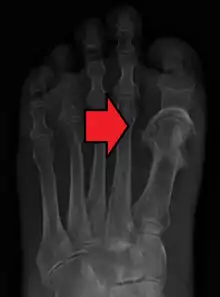

| Fat embolism syndrome | |

![]() | |